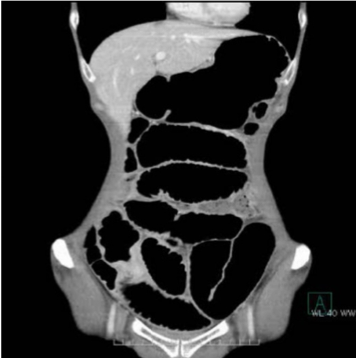

手術前の検査(CT検査)

CT写真の黒い部分が空気です。左側の写真では腸閉塞で太く腫れあがっている腸でおなかの中が充満しています。

別の断面の写真(右側)では癒着により細くなった腸管を認めます(◯)。ここが腸閉塞の原因だとわかります。